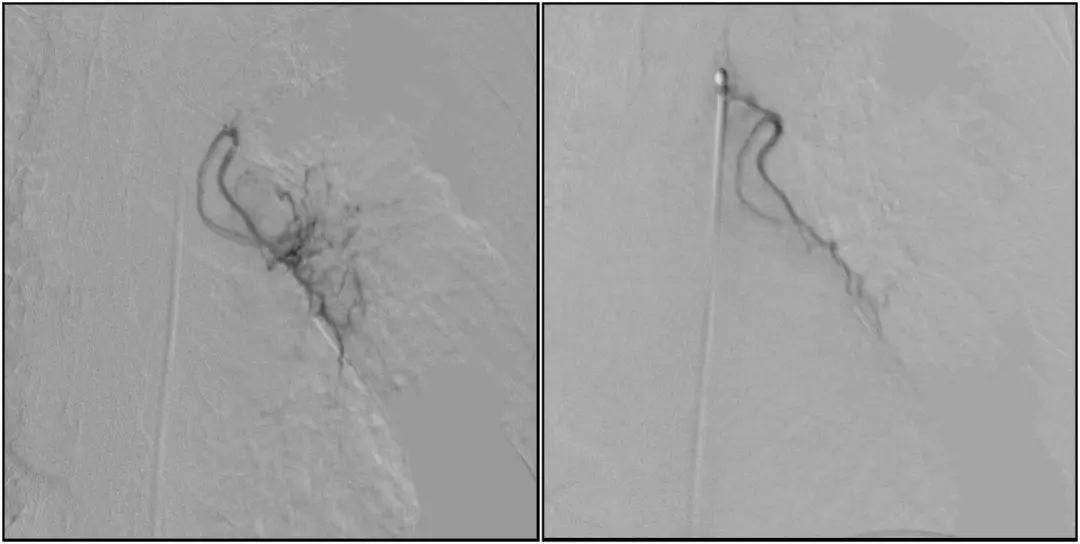

在微導絲的配合下,先后分別超選擇①至3支左側支氣管動脈腫瘤供血動脈,經(jīng)微導管推注栓塞微粒球栓塞腫瘤動脈。栓塞結束后,再次用移動式平板介入中C做造影檢查,見腫瘤染色消失。

術前術后對比影像